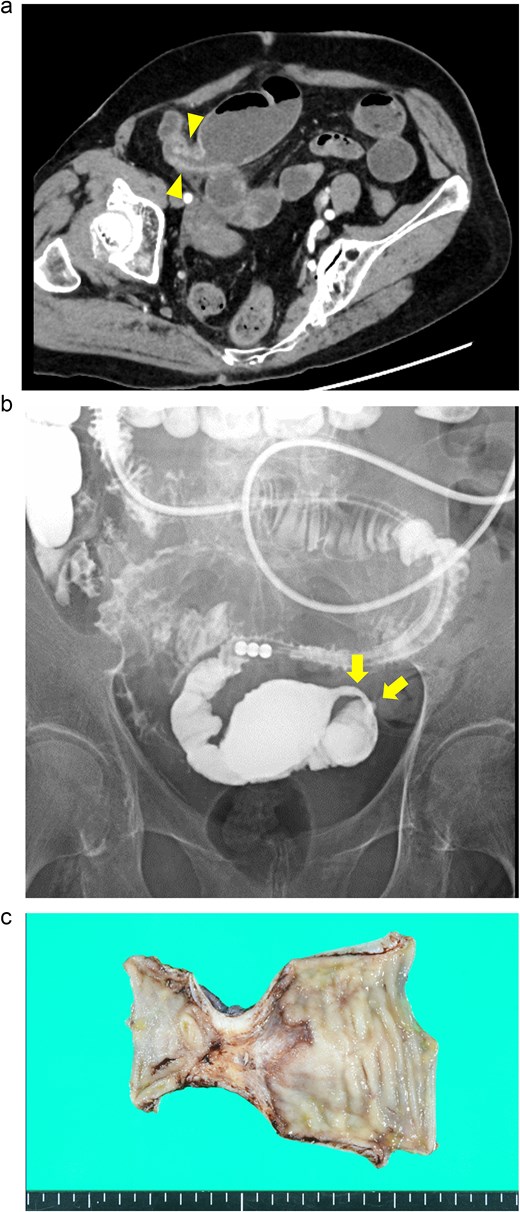

An 82-year-old man presented with recurrent nausea and abdominal pain that had persisted for 3 days. His vital signs were stable, and laboratory test results were as follows: a normal WBC count (3500/μl), elevated CRP concentration (35.4 mg/dl), slight anemia (Hb level:11.7 g/dl), normal Lac concentration (0.8 mmol/L), elevated BGL (259 mg/dl), and elevated HbA1c level (7.3%). Plane CT revealed a segmental stricture without wall thickening in the distal ileum. His proximal small bowel was dilated, and increased attenuation was observed within the adjacent mesenteric fat (Fig. 3a). No HPVG or mesenteric emphysema was observed. The preliminary diagnosis was enteritis without bowel ischemia. The patient was initially tolerant of the conservative treatment and discharged. However, abdominal pain recurred 5 days after discharge, necessitating readmission. Because his symptoms of nausea/vomiting and abdominal pain gradually worsened, a long intestinal tube was placed for luminal decompression. Fluoroscopy revealed segmental, irregular, patchy luminal narrowing of the distal ileum (Fig. 3b). Exploratory laparoscopy revealed a 12-cm-long segmental bowel stricture 30 cm from the ileocecal valve, which was resected. Pathological examination revealed multiple patchy, longitudinal ulcers, and wall thickening at the stenotic site, with granulocyte infiltration and fibrosis extending from the muscularis mucosae through the proper muscle layer. No signs of tumors or IBD were noted (Fig. 3c). The postoperative course was complicated by aspiration pneumonia and transient abdominal pain without intra-abdominal sepsis. He gradually recovered and was transferred to a satellite hospital for continuing care on the 50th postoperative day. The patient’s clinical course at the satellite hospital was uneventful. By 7 months after surgery, he had not had any recurrences of the abdominal symptoms.

Case 3: (a) Plain CT of the abdomen. The arrows indicate a segmental stricture in the distal ileum. The arrowheads indicate dilatation of the small bowel. (b) Fluoroscopy with a long intestinal tube. The arrows indicate segmental, irregular, patchy luminal narrowing of the distal ileum. (c) Macroscopic view of the resected specimen. Multiple longitudinal ulcers with irregular wall thickening are visible in the affected areas.